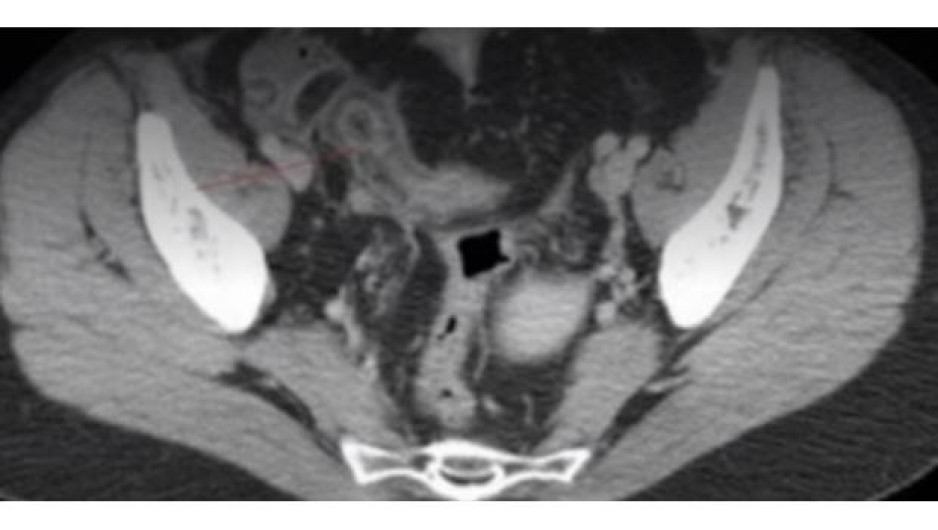

La Revista Británica de Medicina dio a conocer el caso de una mujer de 41 años de edad, a la que se le diagnostico con la enfermedad de Crohn, sin embargo con el paso del tiempo y tratamientos, se determinó que contaba con un objeto extraño alojado en su intestino.

Tras no responder el cuerpo de la mujer a los diversos tratamientos para la enfermedad de Chron, se encontraron pedazos de un paquete de catsup en su intestino.

El sobre habría causado heridas en el estomago de la mujer, causando síntomas similares a los de la enfermedad de Chron